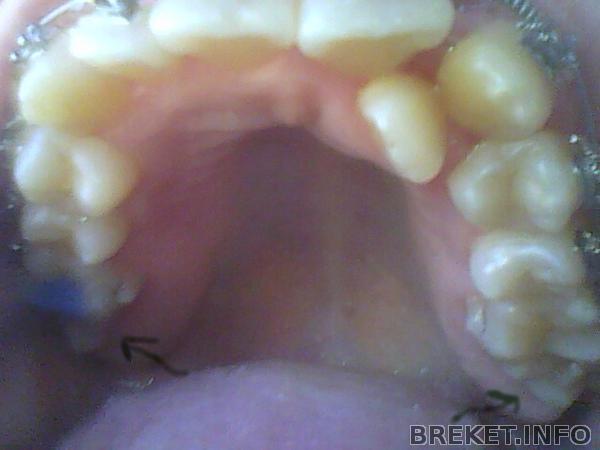

На НЧ установили брекеты через 5 мес. на НЧ отсутствует правая 6-ка. из за чего сместился центр. на фото видно. сейчас ситуация изменилась в худшую сторону. у кого были проблемы с центром? и как решилась эта проблема у вас?

2012-05-01_20.04.25.jpg